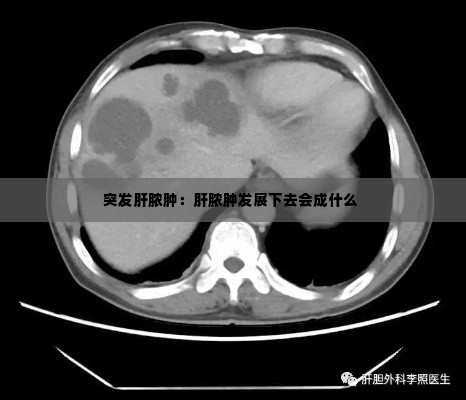

影像学检查:超声波、计算机断层扫描(CT)或磁共振成像(MRI)可以帮助医生看到肝脏内部的脓肿。